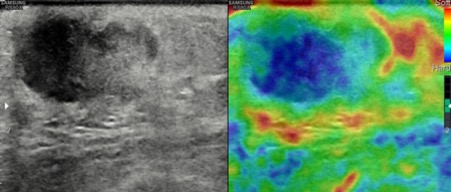

Bilateral Digital mammography , Craniocaudal (CC) and Mediolateral oblique (MLO) view revealed an irregular , high density mass with indistinct margin in retroareolar region with retracted nipple. No microcalcifications was seen. No significant axillary lymph nodes were present. Ultrasound of left breast showed an irregular, heterogeneously hypoechoic mass with indistinct margin and mild posterior acoustic enhancement, measuring about 2.5x1.9x1.3cm in retroareolar region. Internal vascularity was increased on colour doppler. On strain sonoelastogram, the mass showed increased stiffness suggestive of hard consistency. The imaging features are highly suspicious for male breast cancer and thus the mass was classified as BIRADS category 5 lesion and Ultrasound guided biopsy was advised. Patient underwent left modified radical mastectomy and final histopathological report was Invasive Lobular carcinoma. No nipple or lymphovascular invasion was identified.

The imaging features are highly suggestive of male breast cancer and thus the mass was classified as BIRADS category 5